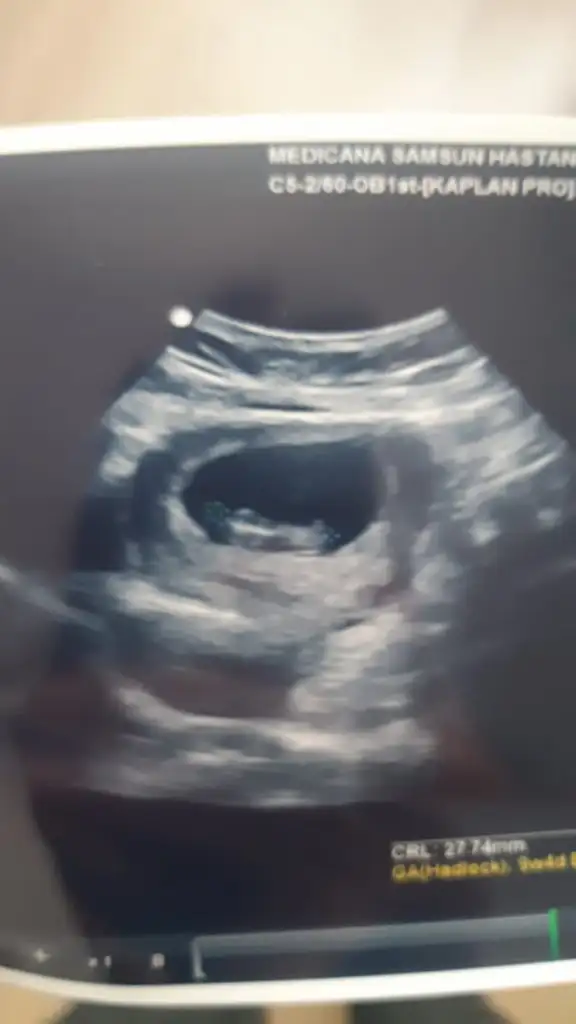

Tam 9. Haftada karından ultrason görüntüsü. Cinsiyeti ne olabilir, ben de merak ettim😊 Pasha22 Pasha22

• IMG-20220414-WA0005.webp

IMG-20220414-WA0005.webp

19,7 KB · Görüntüleme: 113